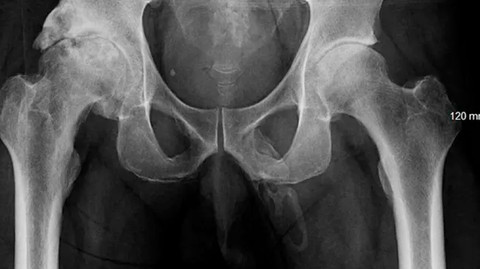

Sinar-X menunjukkan "kalsifikasi luas seperti plak" di sepanjang penis seorang pria.  Foto: Urology Case Reports/Georges El Hasbani

Hasil pemeriksaan menunjukkan, tidak ada pembengkakan prostat. Mereka juga tidak menemukan cairan aneh yang keluar di sekitar alat vital. Dokter lalu melakukan rontgen panggul untuk mencari adanya fraktur. Alih-alih fraktur, mereka justru menemukan pertumbuhan tulang di tempat yang tak terduga, yakni penis pria tersebut.

Dokter mendiagnosis pasien dengan osifikasi penis, kondisi langka ketika struktur tulang ekstraskeletal terbentuk di dalam penis karena akumulasi garam kalsium di jaringan lunak organ tersebut. Sayang, korban menolak pemeriksaan dan perawatan lebih lanjut.